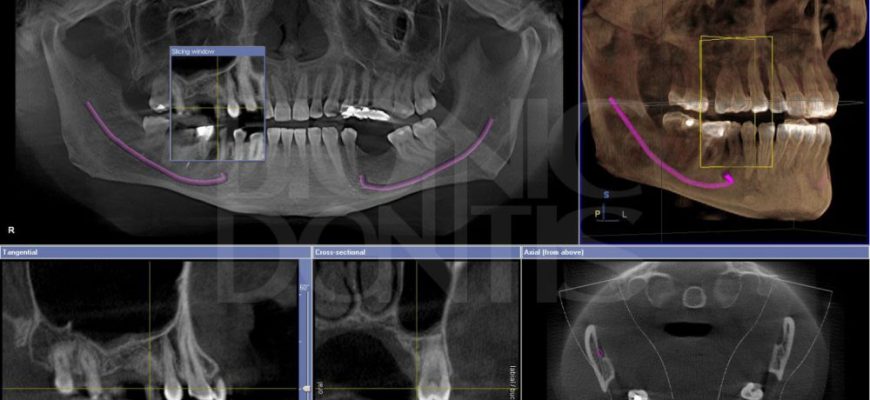

ИИ в стоматологии: Революция в анализе КТ и 3D планировании Стоматология, как и многие другие области медицины, переживает сейчас период бурного развития

ИИ в стоматологии: от снимка к диагнозу ⎻ личный опыт анализа КТ Приветствую вас, дорогие читатели! Сегодня мы погрузимся в захватывающий мир применения